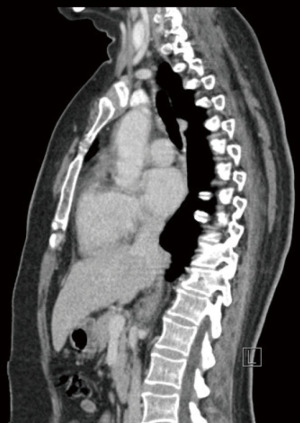

Retrospectively, we reviewed the patient’s mammogram, MRI and CT scan. All the images were consistent with a bilateral RS which is more obvious on the right side as the muscle fibers were longer and wider (Figures 2-4).